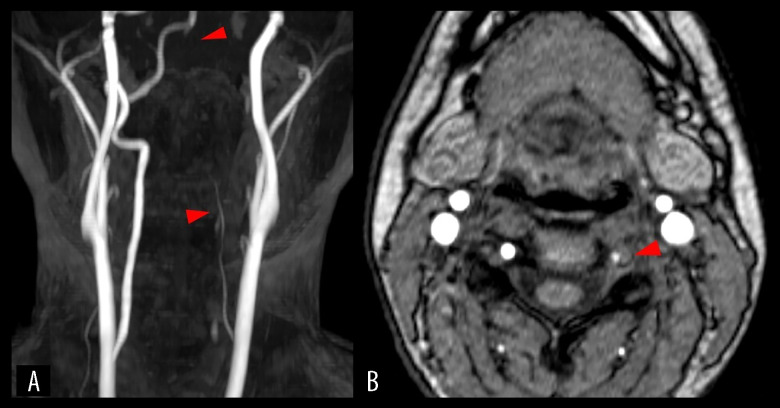

椎动脉夹层(VAD)是青壮年缺血性卒中的重要病因,通常与机械应激源(如创伤、颈部突然运动或剧烈体育活动)有关。虽然电子游戏在传统上并不被认为是一种风险因素,但互动健身游戏的日益流行却引起了人们对其潜在健康影响的关注。病例报告:我们报告了一名25岁的久坐女性,无血管危险因素,她在玩家庭健身视频游戏Ring Fit Adventure(任天堂公司)时,使用基于阻力的控制器进行重复的头顶推拉动作时,出现了急性左侧颈部疼痛。两天后,她突然出现左侧麻木和视觉障碍。神经学检查显示左侧同义性偏视和半感觉缺陷。脑MRI显示右侧枕叶急性梗死,磁共振血管造影显示右侧大脑后动脉闭塞和左侧椎动脉夹层伴壁内血栓。她成功地接受了血管内取栓和动脉内溶栓,随后接受了双重抗血小板治疗。她的症状明显改善,出院时仅有轻度视野缺损。随访时影像学显示血管重构。没有发现潜在的血管病变或血栓形成前状况。结论:本病例强调,即使是看似良性的健身视频游戏也可能施加足够的机械应力来触发VAD,特别是在未经训练的个体中。虽然时间上的联系暗示了一种潜在的联系,但因果关系无法确定。随着家庭健身游戏越来越受欢迎,对于临床医生和公众来说,重要的是要意识到,以前久坐不动的人可能会因突然剧烈运动而出现罕见但严重的血管并发症。

BACKGROUND Vertebral artery dissection (VAD) is an important cause of ischemic stroke in young adults and is often associated with mechanical stressors such as trauma, sudden neck movements, or intense physical activity. While video games are not traditionally recognized as a risk factor, the increasing popularity of interactive fitness games calls for attention to their potential health implications. CASE REPORT We present the case of a 25-year-old sedentary woman with no vascular risk factors who developed acute left-sided neck pain while performing repetitive overhead pushing and pulling movements using a resistance-based controller during gameplay with Ring Fit Adventure (Nintendo Co., Ltd.), a home fitness video game. Two days later, she experienced sudden-onset left-sided numbness and visual disturbance. Neurological examination revealed left homonymous hemianopia and hemisensory deficits. Brain MRI revealed an acute infarct in the right occipital lobe, and magnetic resonance angiography showed right posterior cerebral artery occlusion and dissection of the left vertebral artery with intramural thrombus. She underwent successful endovascular thrombectomy and intra-arterial thrombolysis, followed by dual antiplatelet therapy. Her symptoms improved markedly, and she was discharged with only mild visual field defect. Imaging at follow-up demonstrated vascular remodeling. No underlying vasculopathy or prothrombotic condition was identified. CONCLUSIONS This case highlights that even a seemingly benign fitness video game may exert sufficient mechanical stress to trigger VAD, particularly in untrained individuals. While the temporal association suggests a potential link, causality cannot be definitively established. As home fitness gaming becomes increasingly popular, it is important for both clinicians and the general public to be aware of rare but serious vascular complications that may arise from sudden, strenuous activity in previously sedentary individuals.